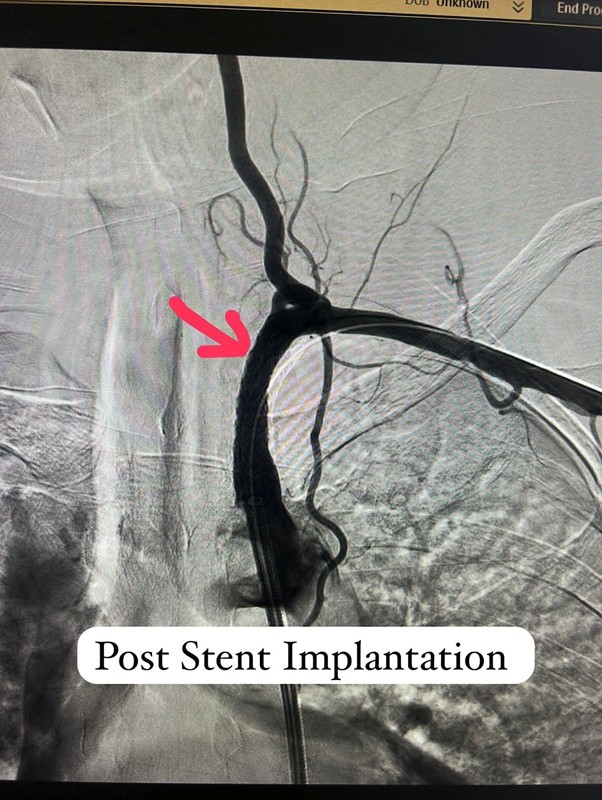

After a few weeks of medical therapy, a repeat CT Angiography showed partial recanalization of the previously occluded subclavian artery, indicating a positive response to treatment. To further define the anatomy and plan intervention precisely, Digital Subtraction Angiography (DSA) was performed. Based on these findings, Dr. Ingle successfully carried out a subclavian artery angioplasty, restoring critical blood flow to the affected limb and reducing future neurological risk.